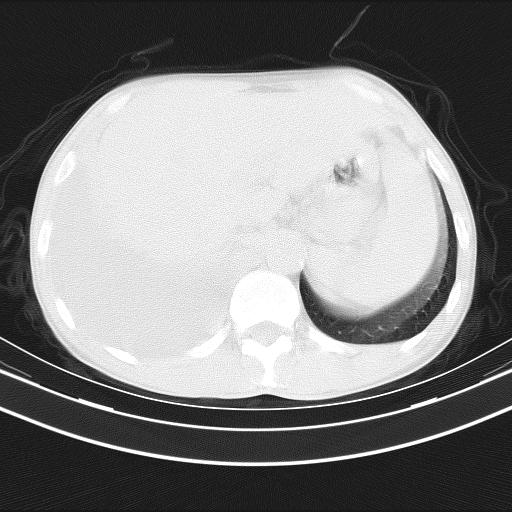

男性,44岁,结核病史多年。现胸闷气短,咳嗽,偶咳血。

右侧胸腔积液

右肺下叶不张

双肺多发结节影最分空洞形成考虑占位不除外结核

双肺陈旧性病变

1、右侧大量胸腔积液伴右肺压缩性膨胀不全,建议抽液治疗后复查 2、两肺继发性tb伴空洞形成。

1)两肺继发性肺结核伴空洞形成,左肺多发性结核球。2)右侧大量胸腔积液伴右肺部分膨胀不全。3)纵隔淋巴结肿大。

1,双肺多发结节 并空洞影改变, 左侧胸腔积液并部分包裹, 结合原病史首先考虑结核. 但也不除外其它.

2,左侧有一根肋骨陈旧性骨折? 建议追查 .

吉大一院胸水抽检结果:结核性胸水